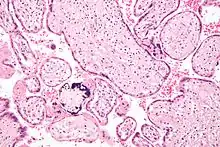

Micrograph of CMV placentitis Micrograph of CMV placentitis